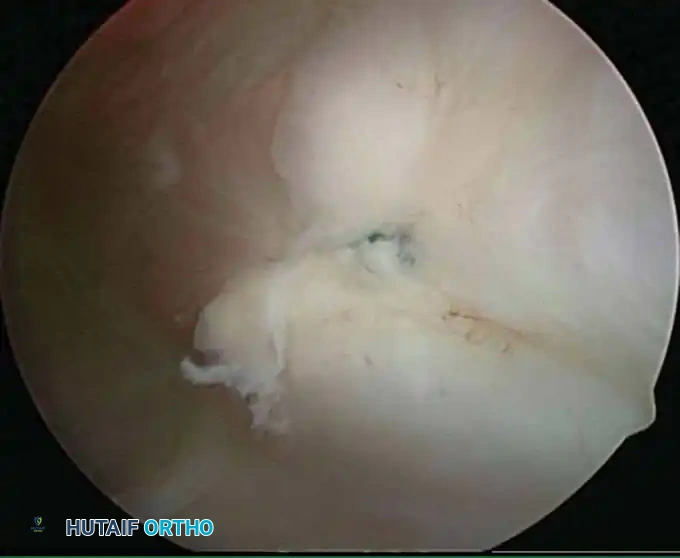

Once diagnostic evaluation is complete and hemostasis is secured, the therapeutic phase commences. Whether performing a SLAP repair, a Bankart stabilization, or a rotator cuff repair, the principles of tissue mobilization, anatomical footprint restoration, and secure biomechanical fixation remain paramount.

Modern arthroscopy relies heavily on suture anchors (biocomposite or all-suture constructs) and advanced arthroscopic knot-tying or knotless techniques. The ability to pass sutures through retracted, fibrotic tissue and secure them under appropriate tension without strangulating the microvascular supply is the hallmark of a master arthroscopist.